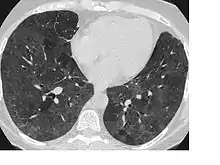

La radiographie pulmonaire, peut montrer une pneumopathie interstitielle diffuse d’aspect micronodulaire (parfois avec des opacités dépolies dans la partie inférieure et moyenne du poumon). Les résultats sont normaux chez environ 10 % des patients. Au scanner, on retrouve des opacités localisées ou diffuse. Les épreuves fonctionnelles respiratoires montre une réduction de la diffusion du monoxyde de carbone (DLCO). Beaucoup de patients ont une hypoxémie de repos, et tous les patients présentent une désaturation à l’exercice physique[3].

Les patients présentant une PHS subaiguë développent progressivement une toux, une dyspnée, une fatigue, une anorexie, une perte de poids et une pleurésie. Les symptômes sont semblables à ceux de la forme aiguë de la maladie, mais moins sévères et durent plus longtemps. Les radiographies pulmonaires, montrent des opacités micronodulaire ou réticulo-nodulaires prédominant le plus souvent dans les zones moyennes et inférieures du poumon[3]. Ces symptômes peuvent être présents chez les patients qui ont présenté des manifestations aiguës répétées.

Sur les radiographies pulmonaires, on note l’apparition dune fibrose progressive avec une perte de capacité pulmonaire affectant en particulier les lobes supérieurs. Les opacités nodulaires ou en nappe ne sont pas présentes. Des aspects caractéristiques de l'emphysème sont trouvés sur de nombreuses radiographies et de nombreux scanners[3].